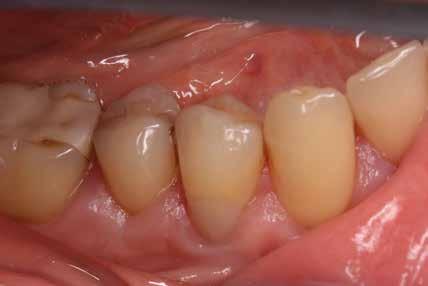

Gyökérkezelendő posterior fogak esetén gyakran találkozunk mély, szubgingivális szuvassággal az approximális területen, melynek szanálása elengedhetetlen előfeltétele a fog endodonciai kezelésének. Az így kialakuló, már kitisztított üreg restaurálása gyakran nehezen kezelhető szituációt teremt a klinikai gyakorlatban. Ezt sokan „endodonciai csonkfelépítésként” kezelik, mely magában rejthet egy ideiglenes jelleget is, holott ez teljesen téves irány. A jelenlegi modern angol nómenklatúra, azaz a „Deep Margin Elevation (DME)” sokkal jobban tükrözi a beavatkozás célját és nehézségét is. Ugyanis a DME a legnehezebb körülmények között elvégzendő adhezív beavatkozásnak minősül. Emellett a teljes, végleges restaurátum sikerességét meghatározza, és kulcsfontosságú a fog megtarthatóságának eldöntési folyamatában: „ha nem tudjuk megfelelően elvégezni, ugyan hogyan akarjuk most vagy a későbbiekben kezelni és megtartani az érintett fogat?” Előadásomban szeretnék bemutatni egy a jelenlegi szakirodalmon alapuló modern, könnyen kivitelezhető protokollt és néhány trükköt, amelyek megkönnyíthetik és kiszámíthatóbbá tehetik ezeknek az erősen destruált fogaknak a helyreállítását.